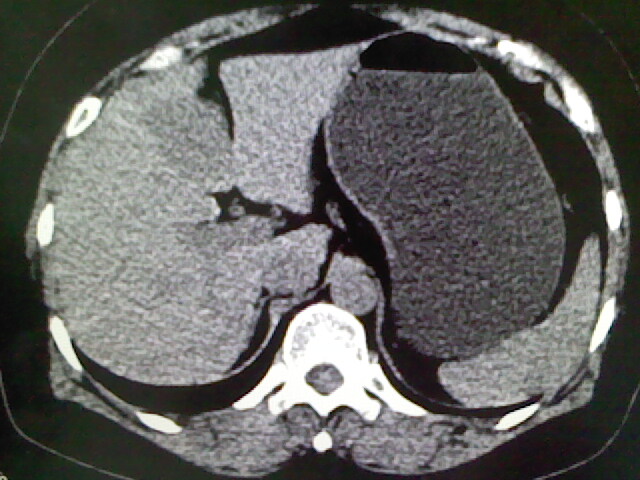

以下是引用卜一在2009-4-2 13:26:00的发言:[br]胆囊颈部结石伴胆囊炎!另:建议增强,待除外肝内占位及胆囊占位!

以下是引用liaoqiang在2009-4-2 16:23:00的发言:[br]胆囊是否切除?胆囊颈区致密影考虑金属夹?结石?肝脏右叶低密度影,考虑增强。